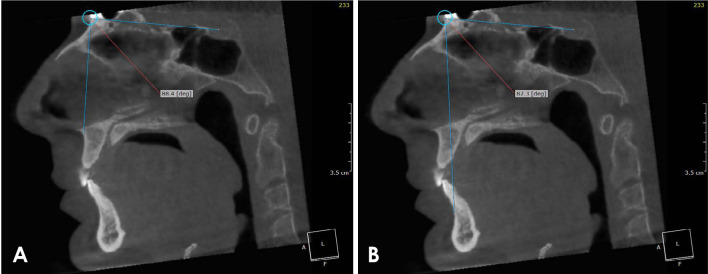

Materials and methods: Forty patients with obstructive sleep apnea were selected from the ear-nose-throat (ENT) outpatient clinic, Faculty of Medicine, Mansoura University. Cone-beam computed tomography was performed for each patient at the end of both inspiration and expiration. Polysomnography was carried out, and the apnea-hypopnea index was obtained. Linear measurements, including cross-sectional area and the SNA and SNB angles, were obtained. Four oral and maxillofacial radiologists categorized pharyngeal and retropalatal airway morphology and calculated the airway length and volume. Continuous data were tested for normality using the Kolmogorov-Smirnov test and reported as the mean and standard deviation or as the median and range. Categorical data were presented as numbers and percentages, and the significance level was set at P<0.05.

Results: The minimal value of the cross-sectional area, SNB angle, and airway morphology at the end of inspiration demonstrated a statistically significant association (P<0.05) with the apnea-hypopnea index, with excellent agreement. No statistically significant difference was found in the airway volume, other linear measurements, or retropalatal airway morphology.